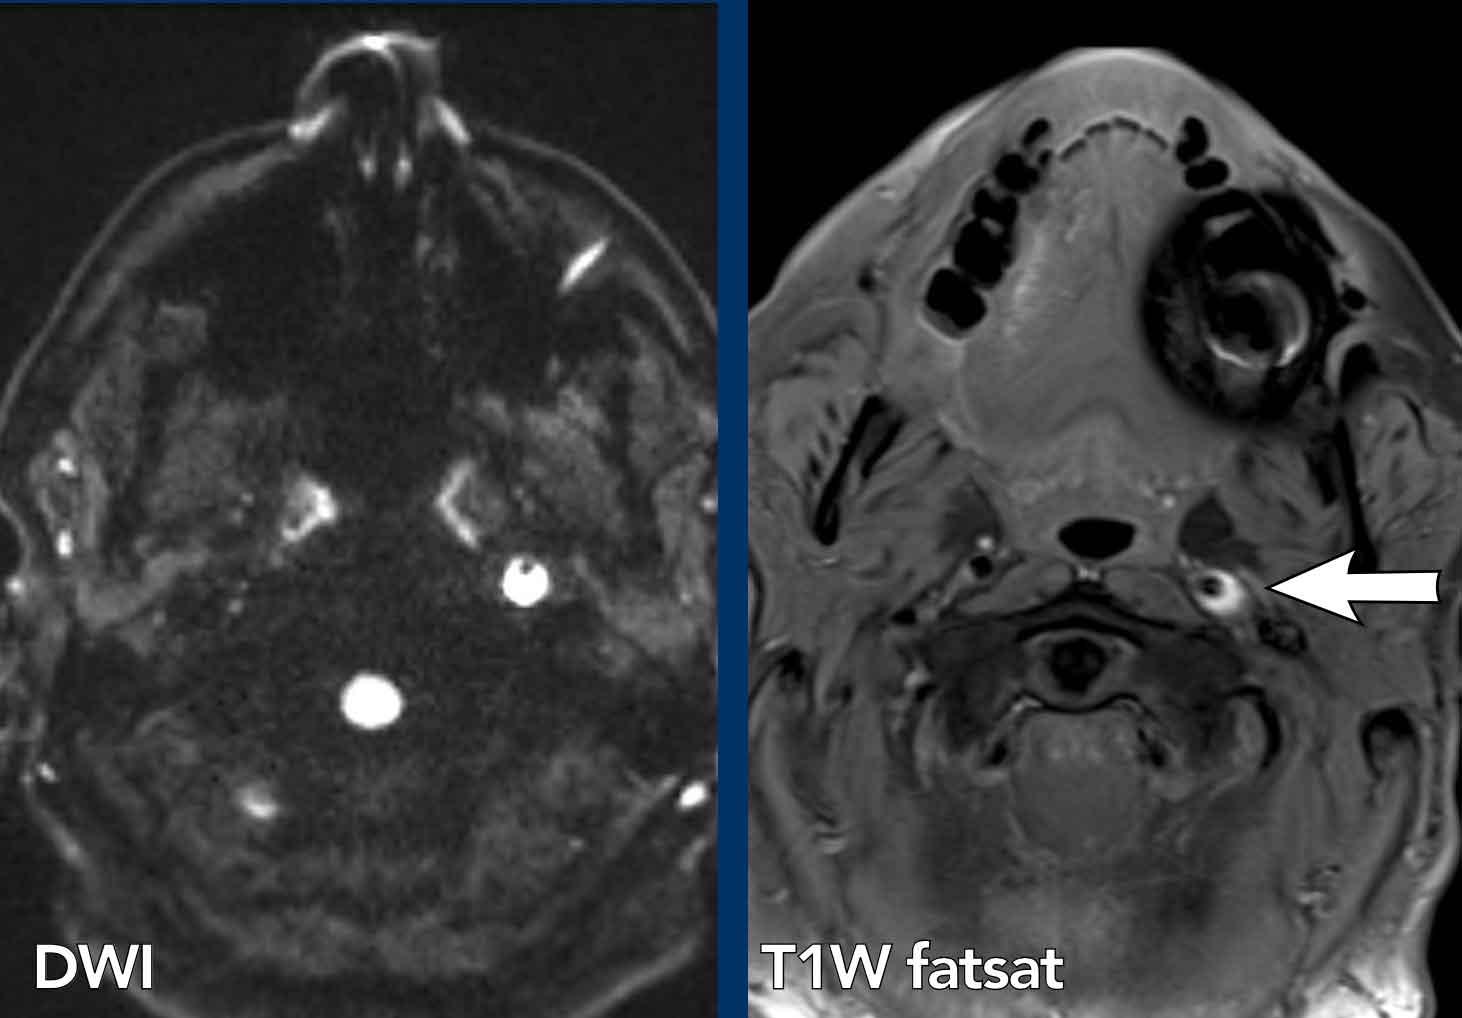

Người đàn ông 45 tuổi khởi phát đột ngột

hội chứng Horner, khó nuốt, mất điều hòa cùng bên, rung giật nhãn cầu và rối loạn cảm giác

cùng bên mặt và đối bên thân mình.

Hình ảnh

Hình ảnh khuếch tán có trọng số

DWI (B1000) và hình ảnh ADC cho thấy hạn chế khuếch tán ở hành tủy bên phải do nhồi máu hành tủy bên.

Continue with the MRA of the neck…

Hình ảnh MRA tương phản cổ (bên phải) cho thấy hẹp động mạch đốt sống phải.

Hình ảnh T1WFS cổ cho thấy tín hiệu hình liềm tăng tín hiệu trong thành động mạch đốt sống phải, điển hình của tụ máu trong thành mạch.

Kết luận

Bóc tách động mạch đốt sống phải gây nhồi máu hành tủy.